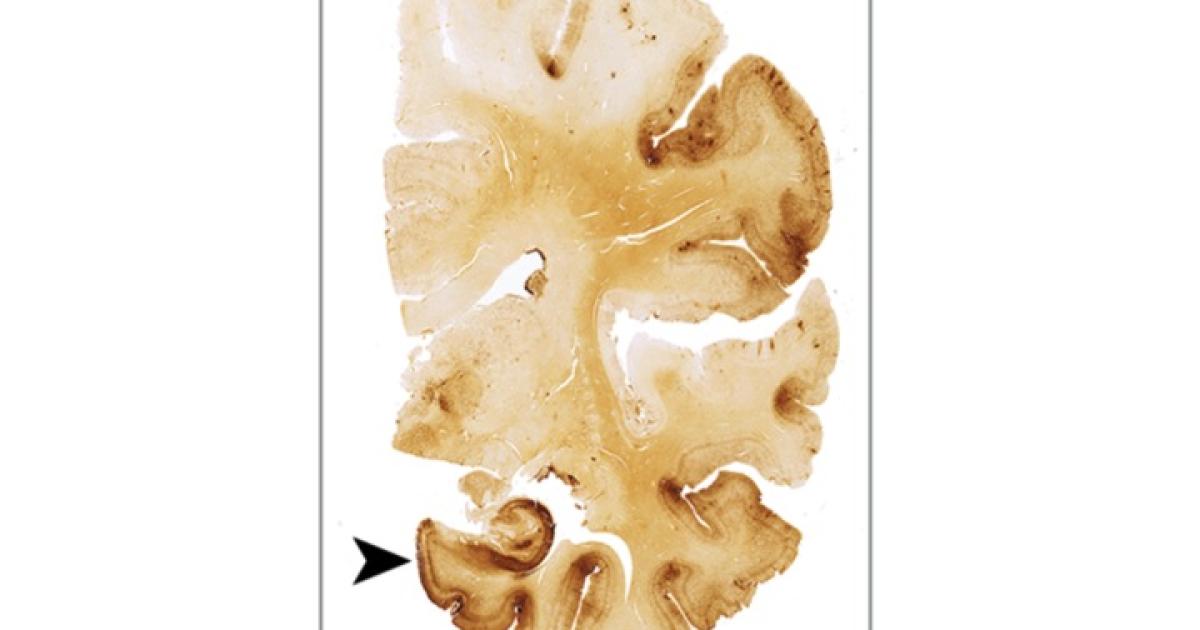

The brains tell the real story, though. Post-mortem brains are analyzed by looking for tell tale signs of brain injury (seen below.) The brain of someone who has CTE looks different under the microscope than a normal brain. The brain trauma creates a destruction of the tissue of the brain, one of the hallmarks of which is a protein called Tau. In the figures below, the presence of Tau is marked by the dark brown color. The more Tau, the worse the symptoms.

There are four stages of CTE. The levels go from mild (I) to severe (IV) can be seen in the figures below. The images on the left are a slice of the whole brain. The image on the right is a magnified (or zoomed in) image of the slice on the left. The pictures below are from the paper released last week in JAMA that analyzed the brains of football players. The stage III and IV brains are from former NFL players.